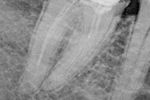

Revisionsbehandlung eines Unterkiefermolaren (37) vor geplanter Überkronung (Dr. Maik Göbbels) Download